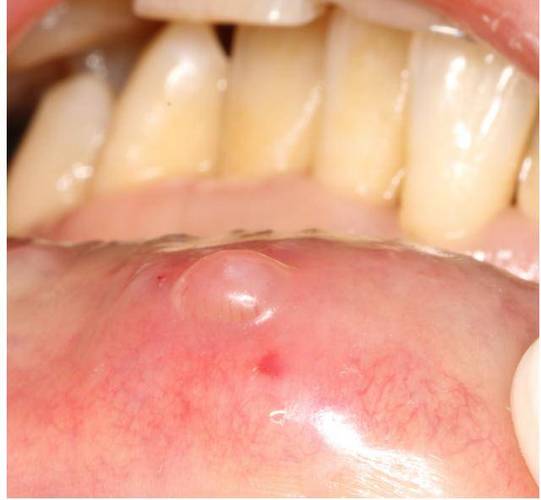

皮样囊肿:

(图片来源网络,侵删)- 原因: 一种先天性囊肿,但较少见。

- 特点: 质地较韧,通常位于口底区域,生长缓慢。